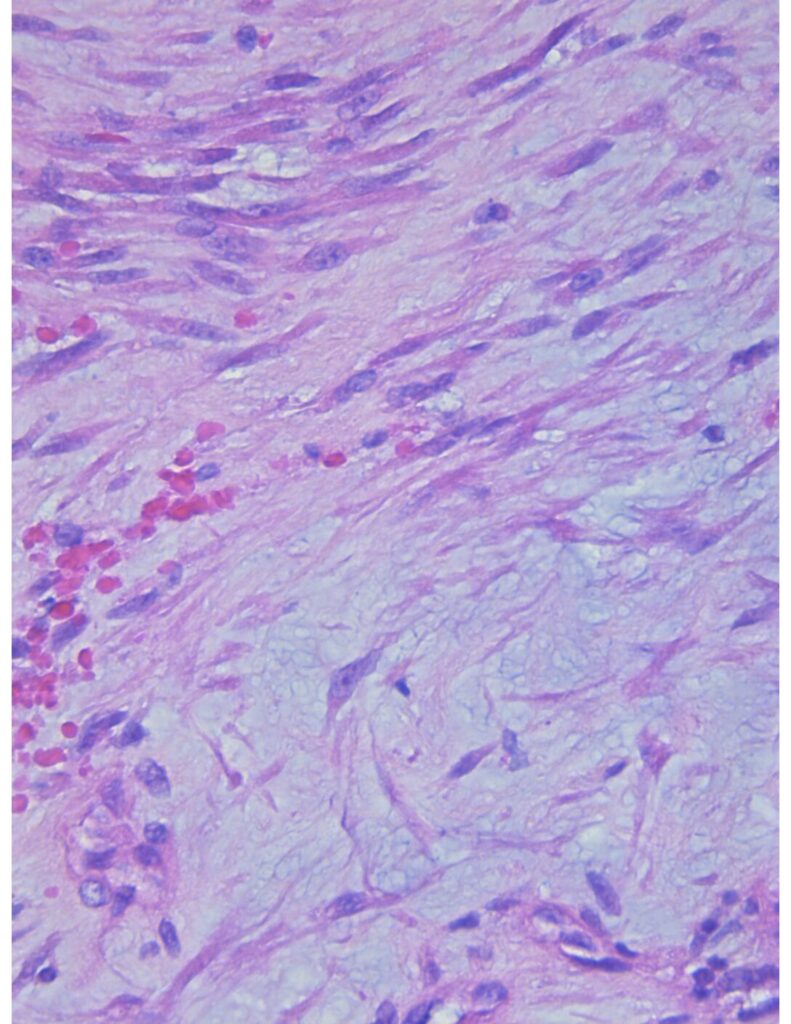

Laboratorio de anatomía patológica

Estamos enfocados en el análisis eficiente de cada muestra en nuestras manos, entendemos que cada uno representa la vida de nuestro paciente y por eso nos enfocamos en la eficiencia, trazabilidad y diagnósticos precisos.